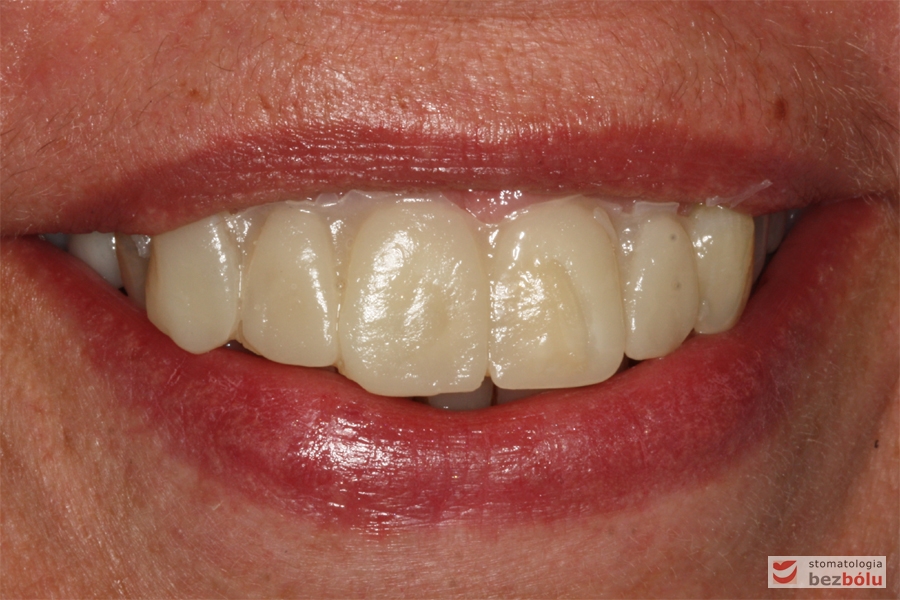

Efekt końcowy leczenia - nowe zęby w uśmiechu

Efekt końcowy leczenia – nowe zęby w uśmiechu